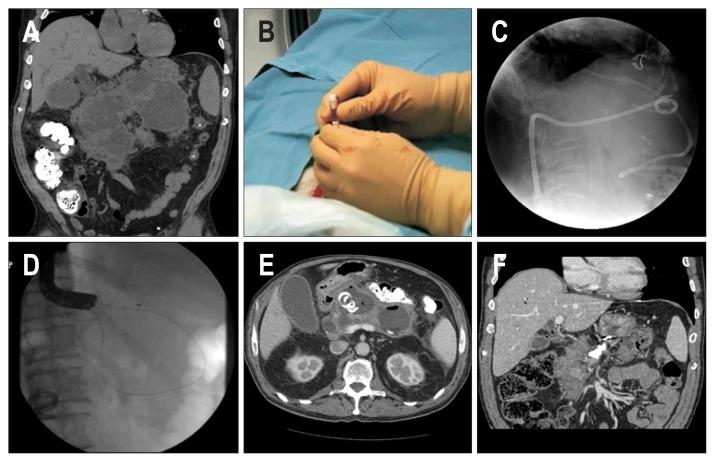

Outcomes of Infected versus Symptomatic Sterile Walled-Off Pancreatic Necrosis Treated with a Minimally Invasive Therapy.

BACKGROUND/AIMS: Acute pancreatitis complicated by walled-off necrosis (WON) is associated with high morbidity and mortality, and if infected, typically necessitates intervention. Clinical outcomes of infected WON have been described as poorer than those of symptomatic sterile WON. With the evolution of minimally invasive therapy, we sought to compare outcomes of infected to symptomatic sterile WON.

We performed a retrospective cohort study examining patients who were undergoing dual-modality drainage as minimally invasive therapy for WON at a high-volume tertiary pancreatic center. The main outcome measures included mortality with a drain in place, length of hospital stay, admission to intensive care unit, and development of pancreatic fistulae.

Of the 211 patients in our analysis, 98 had infected WON. The overall mortality rate was 2.4%. Patients with infected WON trended toward higher mortality although not statistically significant (4.1% vs 0.9%, p=0.19). Patients with infected WON had longer length of hospitalization (29.8 days vs 17.3 days, p<0.01), and developed more spontaneous pancreatic fistulae (23.5% vs 7.8%, p<0.01). Multivariate analysis showed that infected WON was associated with higher odds of spontaneous pancreatic fistula formation (odds ratio, 2.65; 95% confidence interval, 1.20 to 5.85).

This study confirms that infected WON has worse outcomes than sterile WON but also demonstrates that WON, once considered a significant cause of death, can be treated with good outcomes using minimally invasive therapy.